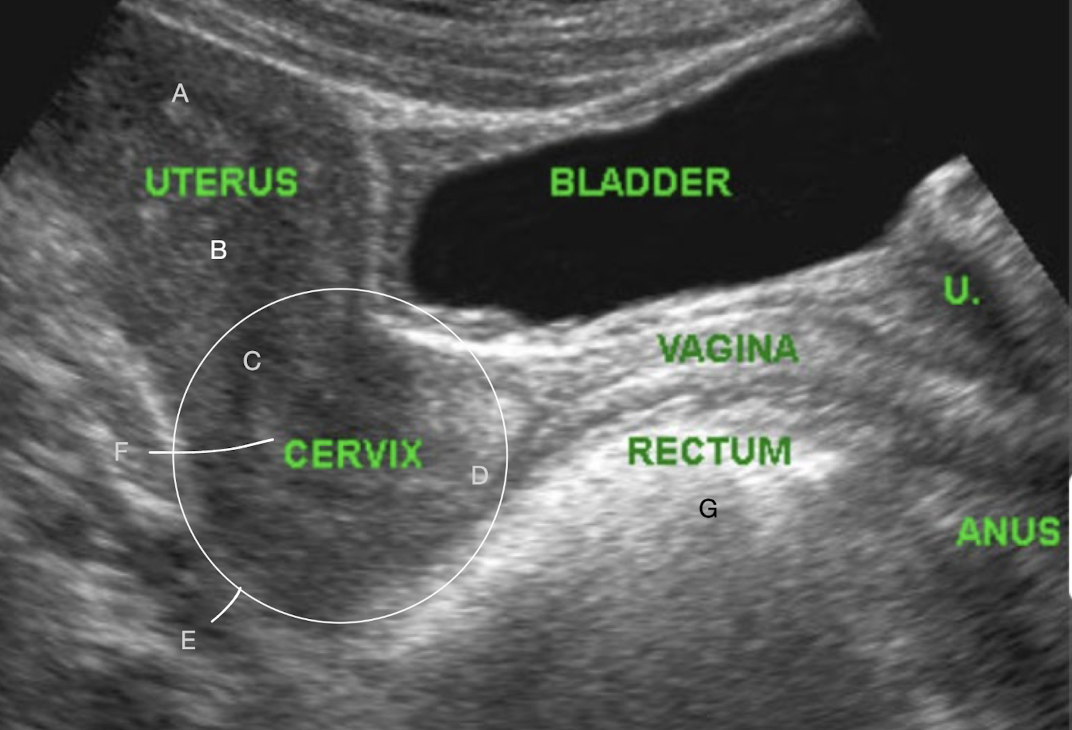

SONO: vagina, cervix, uterus

A?

fundus

B?

body

C?

internal os

D?

external os

E?

LUS

F?

cervical canal

G?

bowel